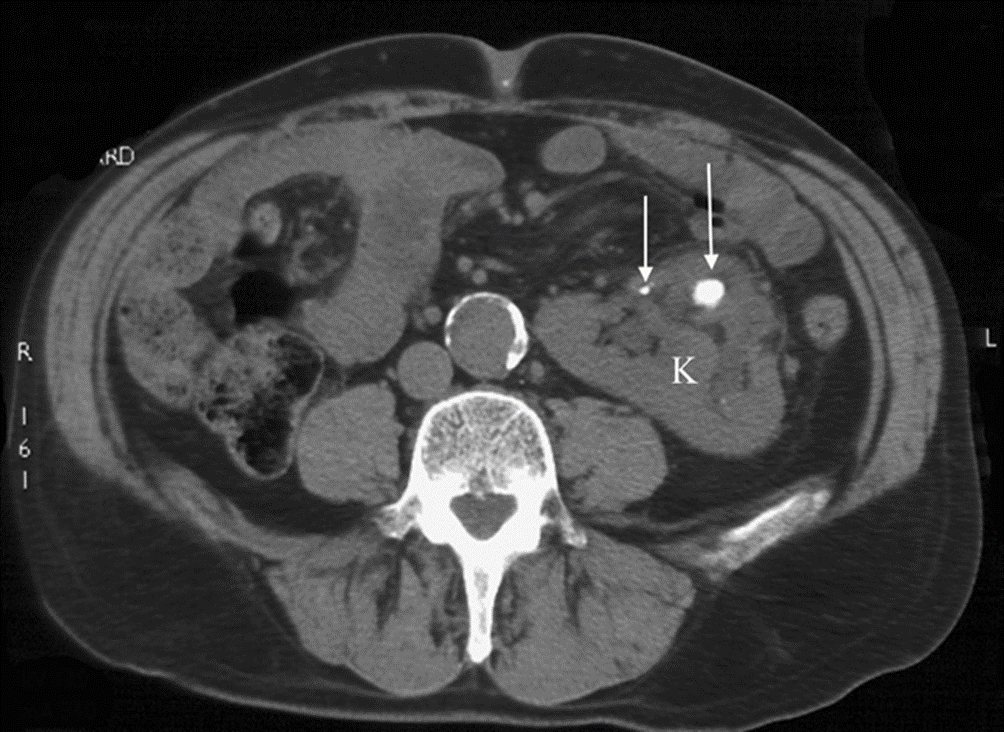

Non-contrast enhanced CT

in a patient with crossed fused ectopia, a renal anatomical variant.

Multiple stones were demonstrated (arrows), allowing accurate planning of his lithotripsy treatment.